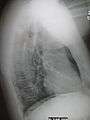

Right upper lobe pneumonia as marked by the circle.- Left upper lobe pneumonia with a small pleural effusion.

- Right lower lobe pneumonia as seen on a lateral CXR